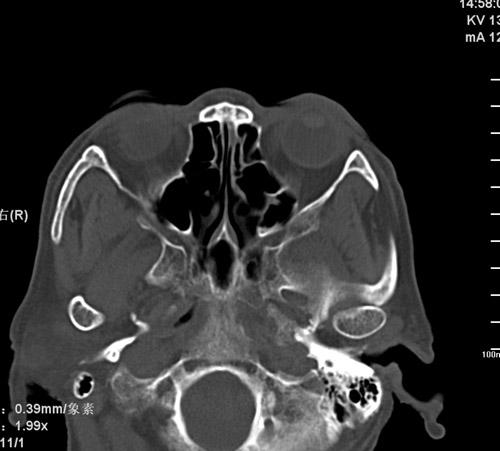

标题: CT17755:女,74 左鼻旁肿胀半年,临床以左上颌窦旁占位行CT [打印本页]

标题: CT17755:女,74 左鼻旁肿胀半年,临床以左上颌窦旁占位行CT

ct考虑鼻前庭囊肿 或鼻翼基底部慢性炎症,左上颌窦少许炎症 请指教

1)考虑左侧鼻前庭囊肿并感染。2)双侧上颌窦炎。

左侧鼻前庭囊肿并感染。双侧上颌窦炎。支持